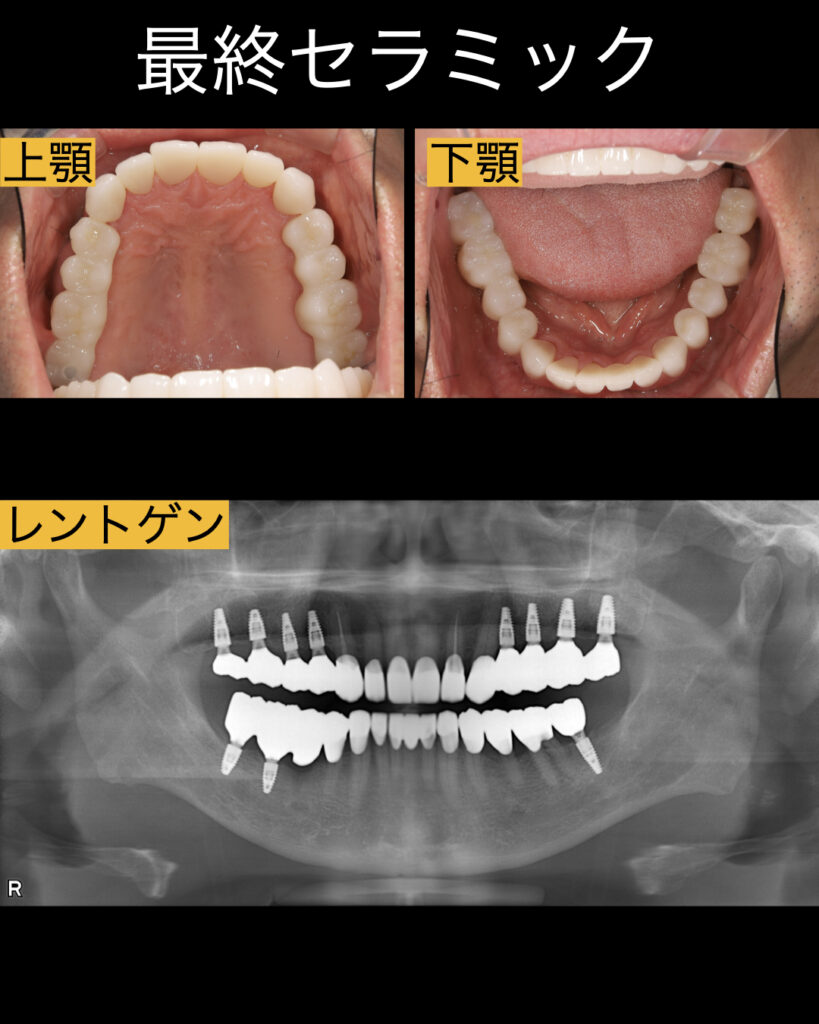

1ヶ月後、インプラント手術はサージカルガイドで行いました。上顎の骨は柔らかく、インプラントは少し多めの左右4本づつの合計8本、下は骨が硬くインプラントは少なめの合計3本。インプラントは多ければ良いというわけでなく。適切な部位に適切な本数を埋入しなければなりません。

今回の症例でもさサージカルガイドを使用し、上顎8本のインプラント埋入は約1時間で終了。下は30分ほどで終了しました。(骨の状態が良かったので歯茎を開けなく短時間ですみました)。

| 治療内容 | 上顎奥8本のインプラント、下顎3本のインプラント |